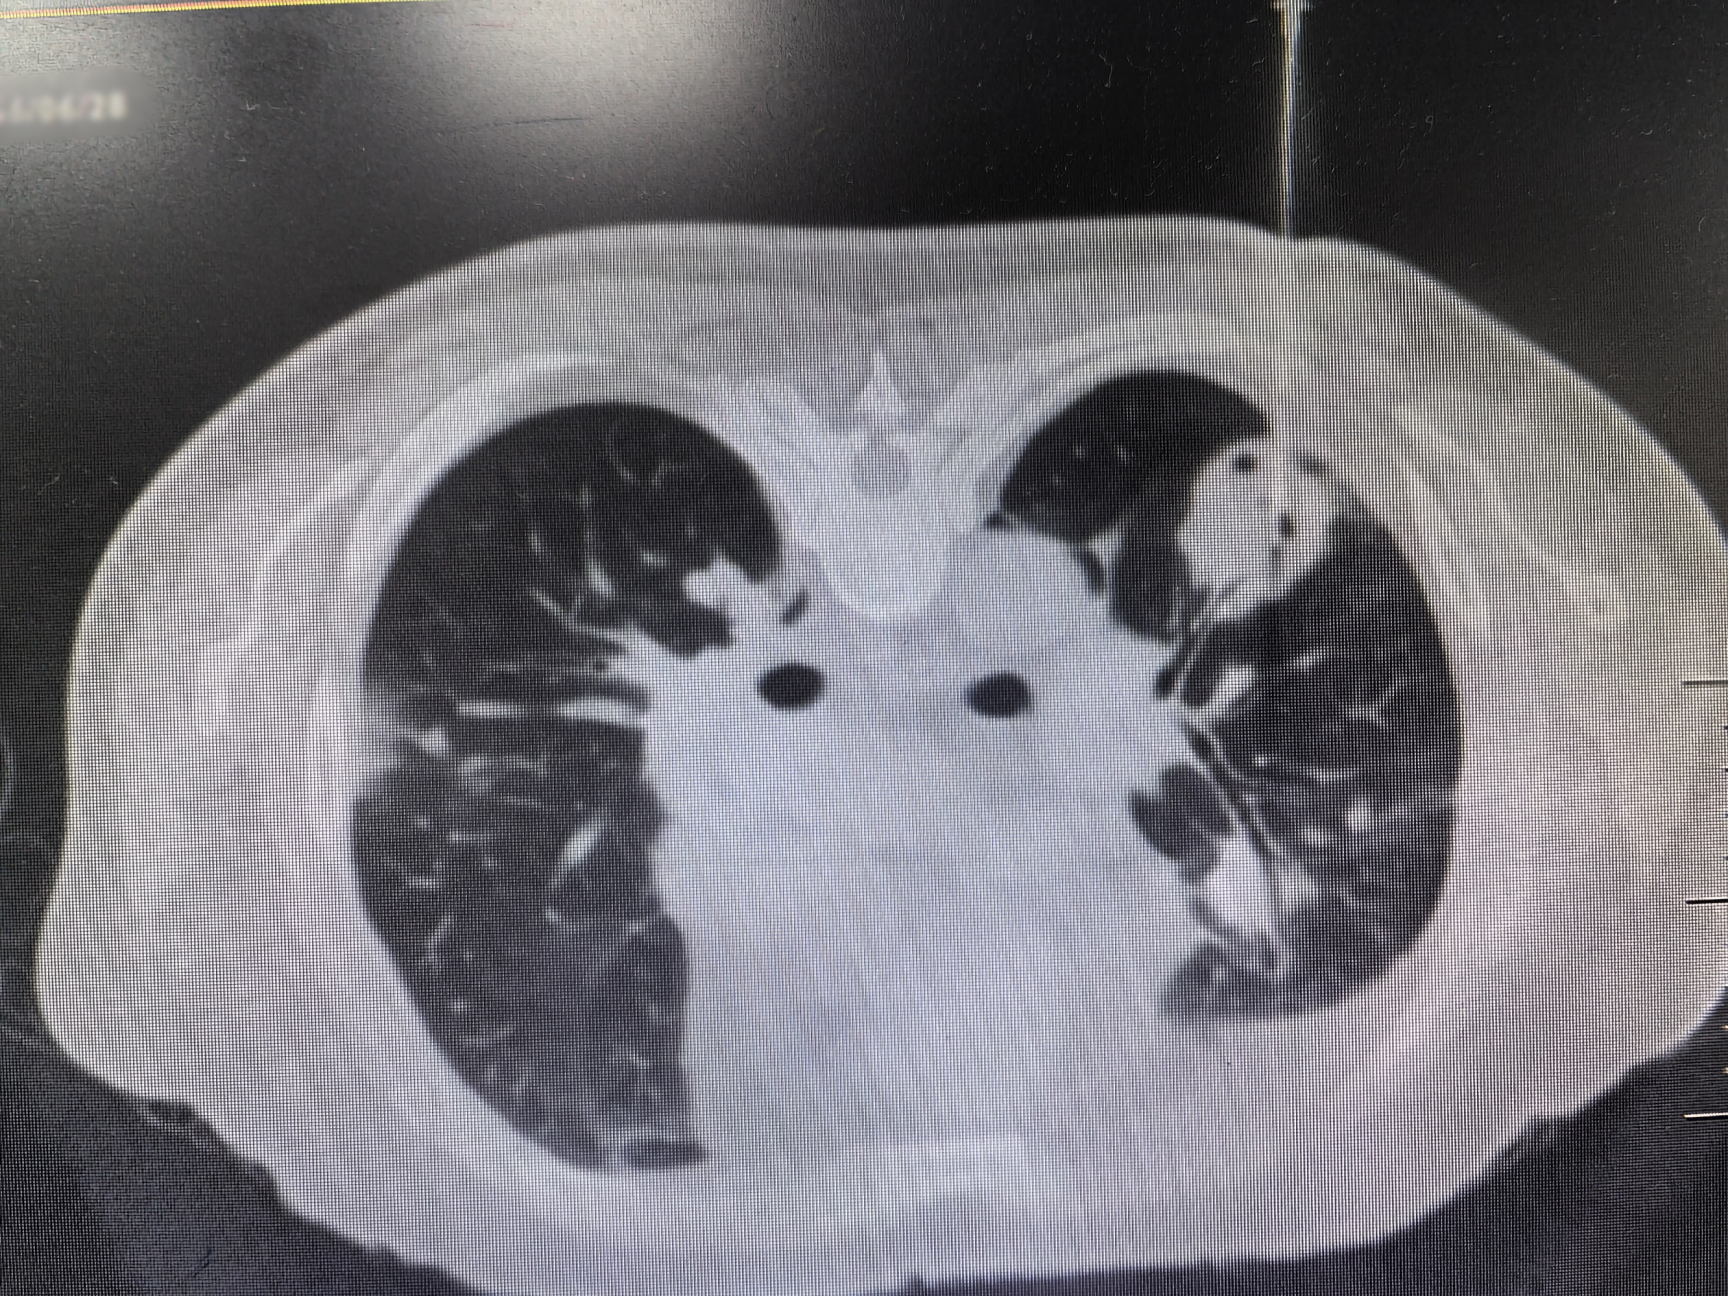

与患者反复沟通病情后,患者最终同意再次进行肺活检。完善术前检查、排除肺活检禁忌证后,在呼吸介入团队医护配合下,陆霓虹博士为患者实施了高难度“双肺结节同步穿刺活检术”。手术仅用时12分钟,顺利获取病变组织,且患者无并发症。病理检查(ROSE)提示肉芽肿性病变,结合血液c-ANCA阳性,最终确诊为“韦格纳肉芽肿病”(WG)。经对症治疗,患者症状显著好转。

韦格纳肉芽肿病(WG)是一种特殊的坏死性肉芽肿性血管炎,病因不明。病变常累及多个器官,病理表现为肉芽肿性病变,伴血管壁炎症。因WG发病率较低,肺部病变常常被误诊为肺部肿瘤或者肺结核。2024年发表的中国肺结节规范化诊疗专家共识指出,双肺多发结节须进行双肺的活检取材,避免结节漏诊及误诊。双肺同步穿刺技术难度较高,对操作医师的熟练程度、操作技术水平均有要求。